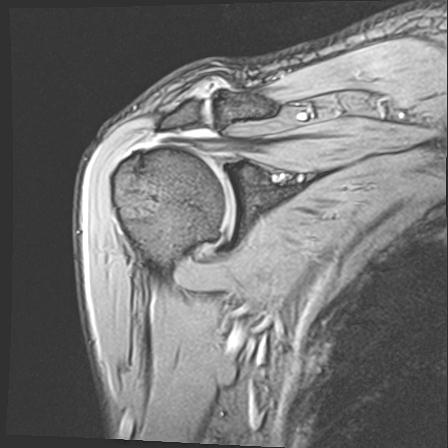

60058 3/9 11/4 右肩 2R+MRI 73歳男性 肩腱板損傷